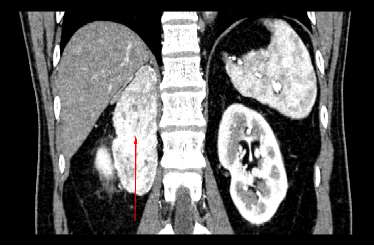

最近,陈先生体检发现占位不断变大,便前往当地医院看诊,才被确诊为右侧肾上腺嗜铬细胞瘤——此时肿瘤已长到10公分,就象一颗大土豆,被下腔静脉等重要血管包绕,成了一颗随时会引爆的“隐形炸弹”。

切除嗜铬细胞瘤的手术充满了挑战,由于肿瘤血供丰富,周围血管密布,稍有不慎就可能引发大出血;更凶险的是,术中若挤压肿瘤,会导致大量激素释放,引发血压骤升,甚至诱发心脑血管意外。

对于这种极富挑战的高难度手术,传统腹腔镜手术难以保证手术的精细度,而国产手术机器人成了破题关键。它的3D视野可放大10-15倍,肉眼难以分辨的微小血管也能分毫毕现;灵活精准的机械臂可以过滤人手抖动,保证精准的切除与缝合操作;因而能将手术风险降至最低。